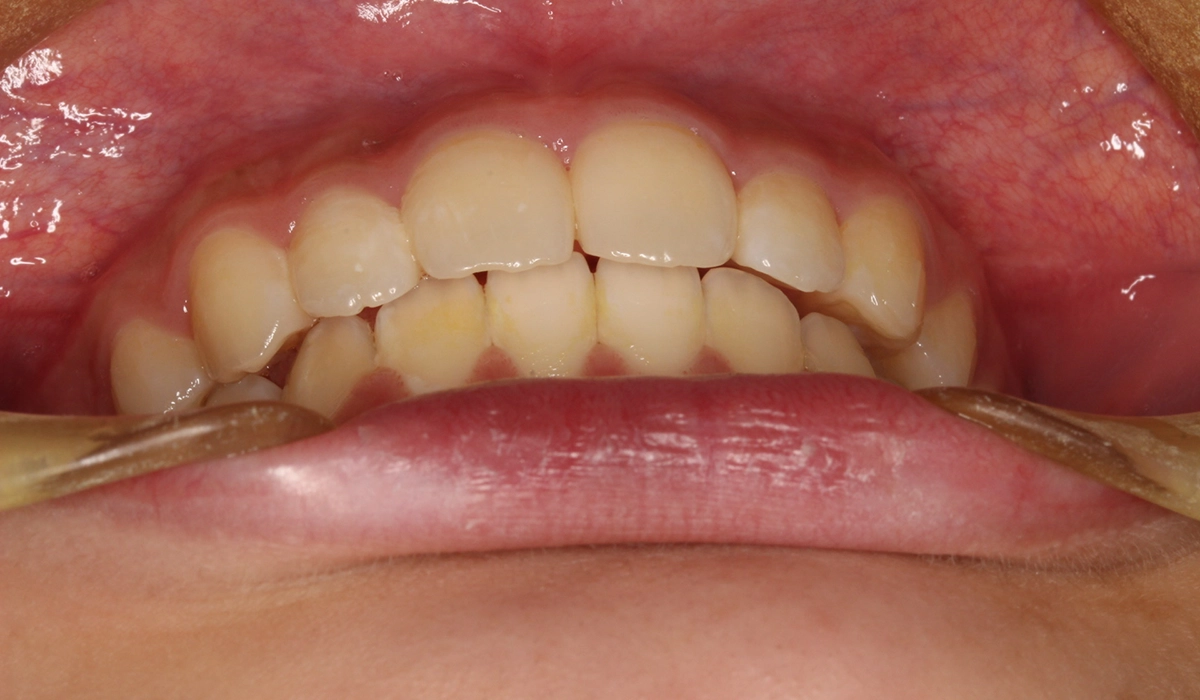

術前:前歯部

術後:前歯部